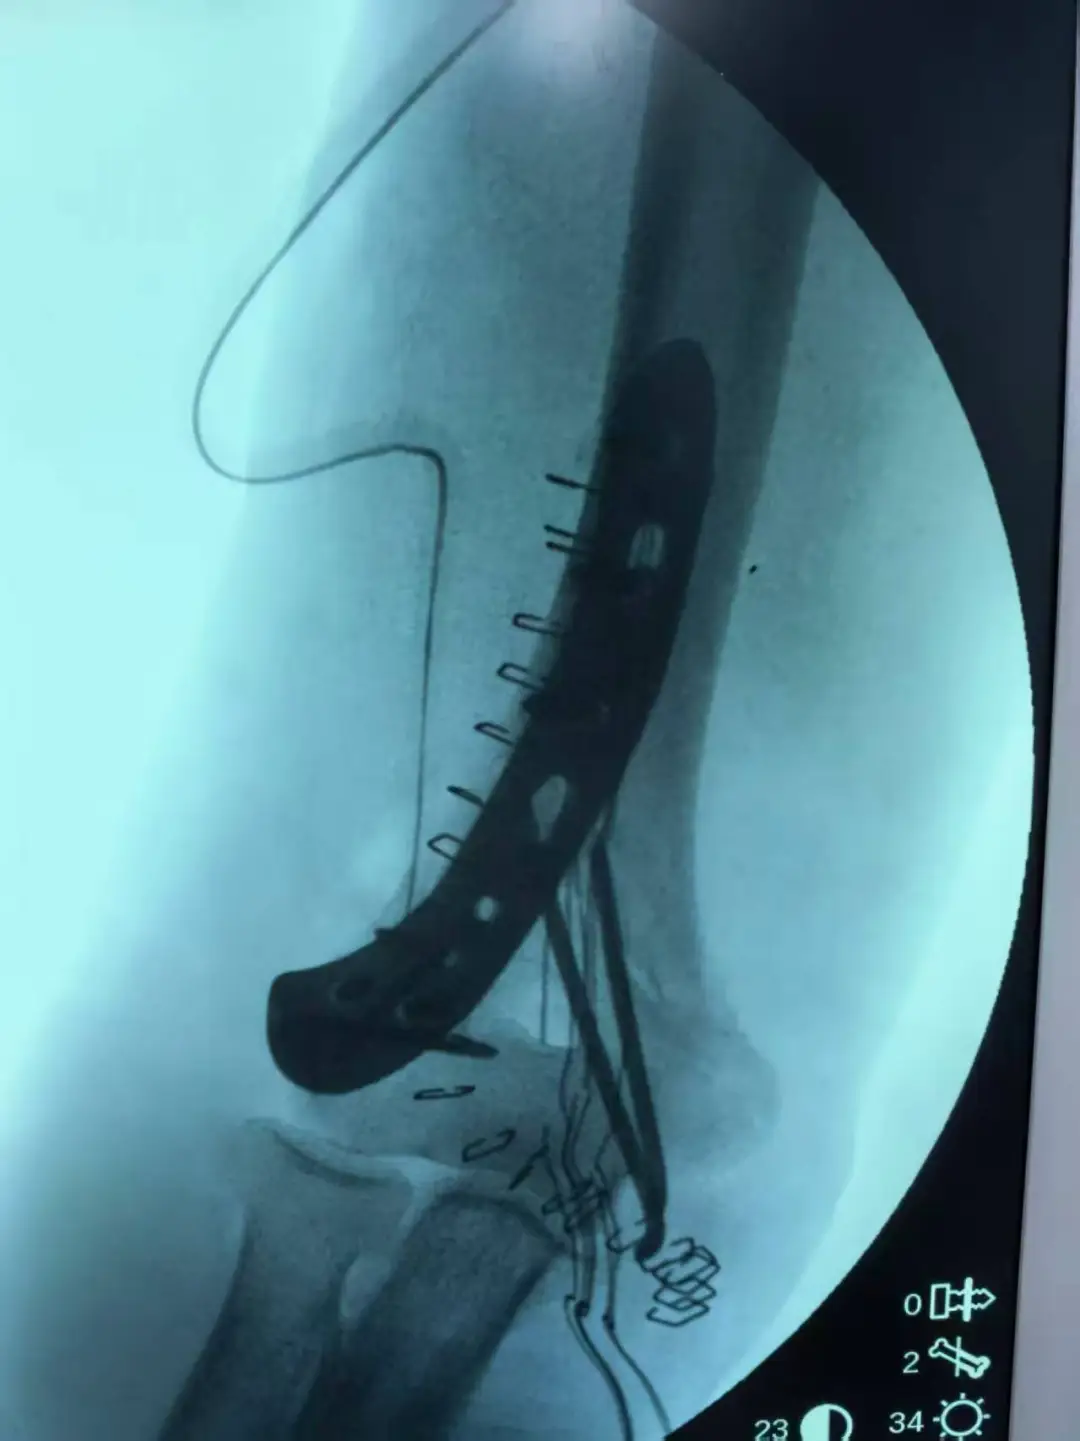

手術的成功離不開三大核心支撐:一是精準解剖復位,如同拼接精密拼圖,王主任和張醫(yī)生憑借豐富經(jīng)驗與嫻熟技巧,將粉碎的關節(jié)面實現(xiàn)解剖級對合,為功能恢復筑牢基礎;二是穩(wěn)固內固定,采用專為肱骨遠端設計的解剖鋼板和螺釘系統(tǒng),為碎骨塊提供堅強支撐,保障術后早期康復鍛煉;三是多學科協(xié)作(MDT),麻醉科、手術室、重癥醫(yī)學科、等科室緊密配合,為患者筑起堅實的生命防線。

57分鐘后,手術圓滿成功。術后影像顯示,粉碎的關節(jié)面完美重建,內固定物位置精準。